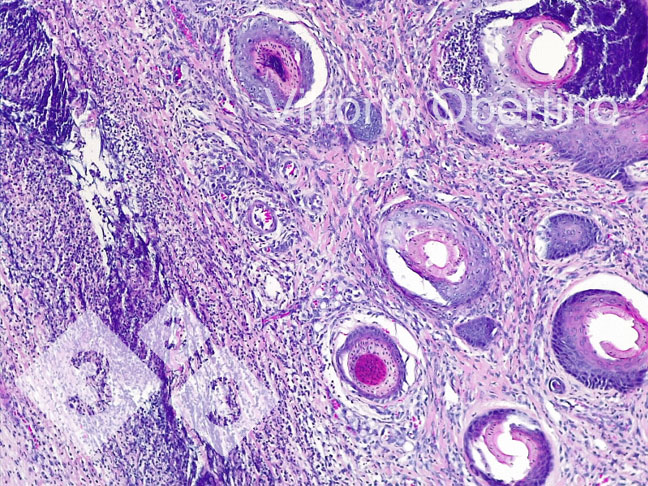

2- Foram enviadas amostras de tecido à Universidade de Torino para verificar se as lesões eram histologicamente compatíveis com as imagens descritas na literatura. (Kuehling et al. 2020).

Figura 9. Pele. Erosão epitelial focal em que a camada superficial é substituída por abundante material eosinofílico amorfo a granular com restos cariorécticos (necrose) e abundantes granulocitos neutrofílicos degenerados e viáveis. Multifocalmente, o epitélio aparece de moderada a marcadamente hiperplásico com hiperqueratose ortoqueratósica de moderada a severa. Também é observada a presença multifocal de crosta. A derme aparece difusa e moderadamente fibrótica.